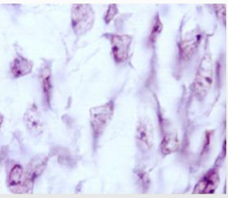

What kind of the tissue is this and where is it located?

Mesenchymal tissue

Located in the Embryonic connective tissue